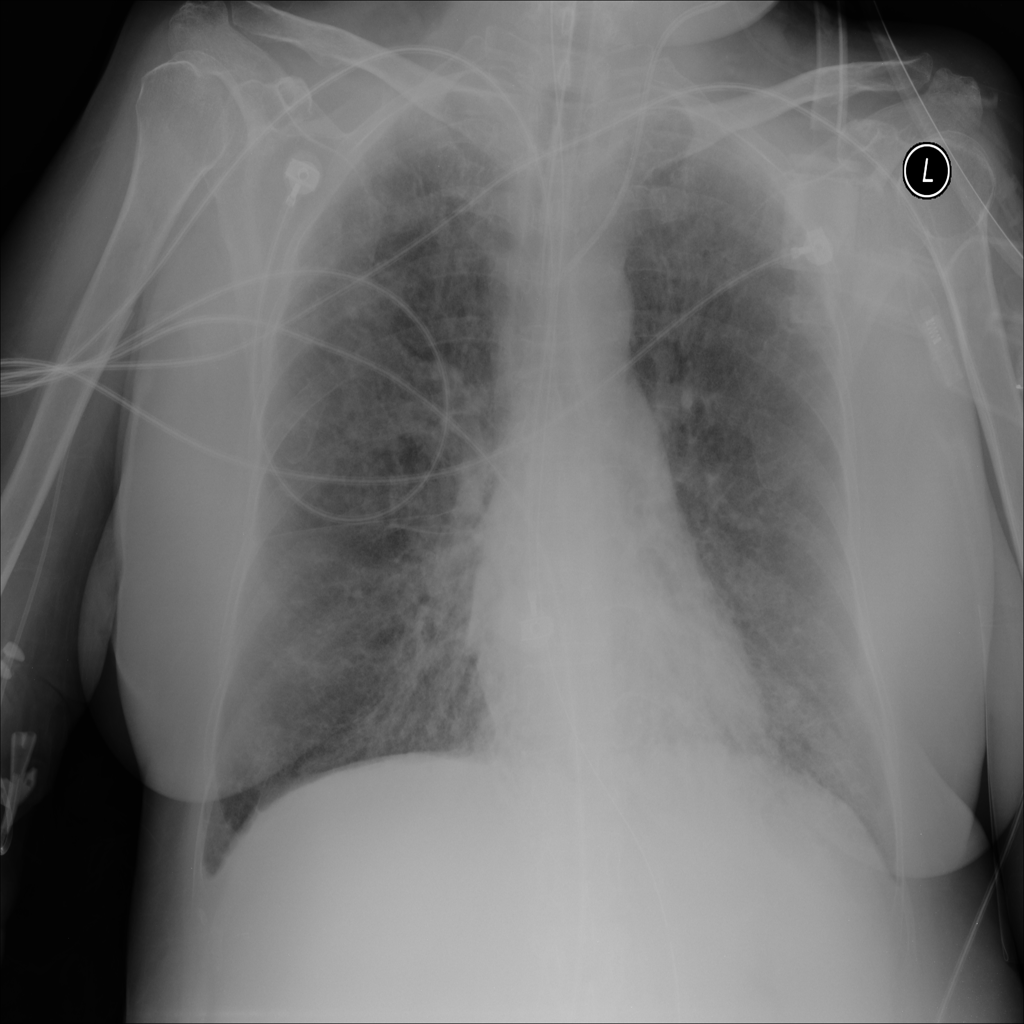

PAT-C1A7 · IMG-004Consolidation

PAT-C1A7 · IMG-004

PA